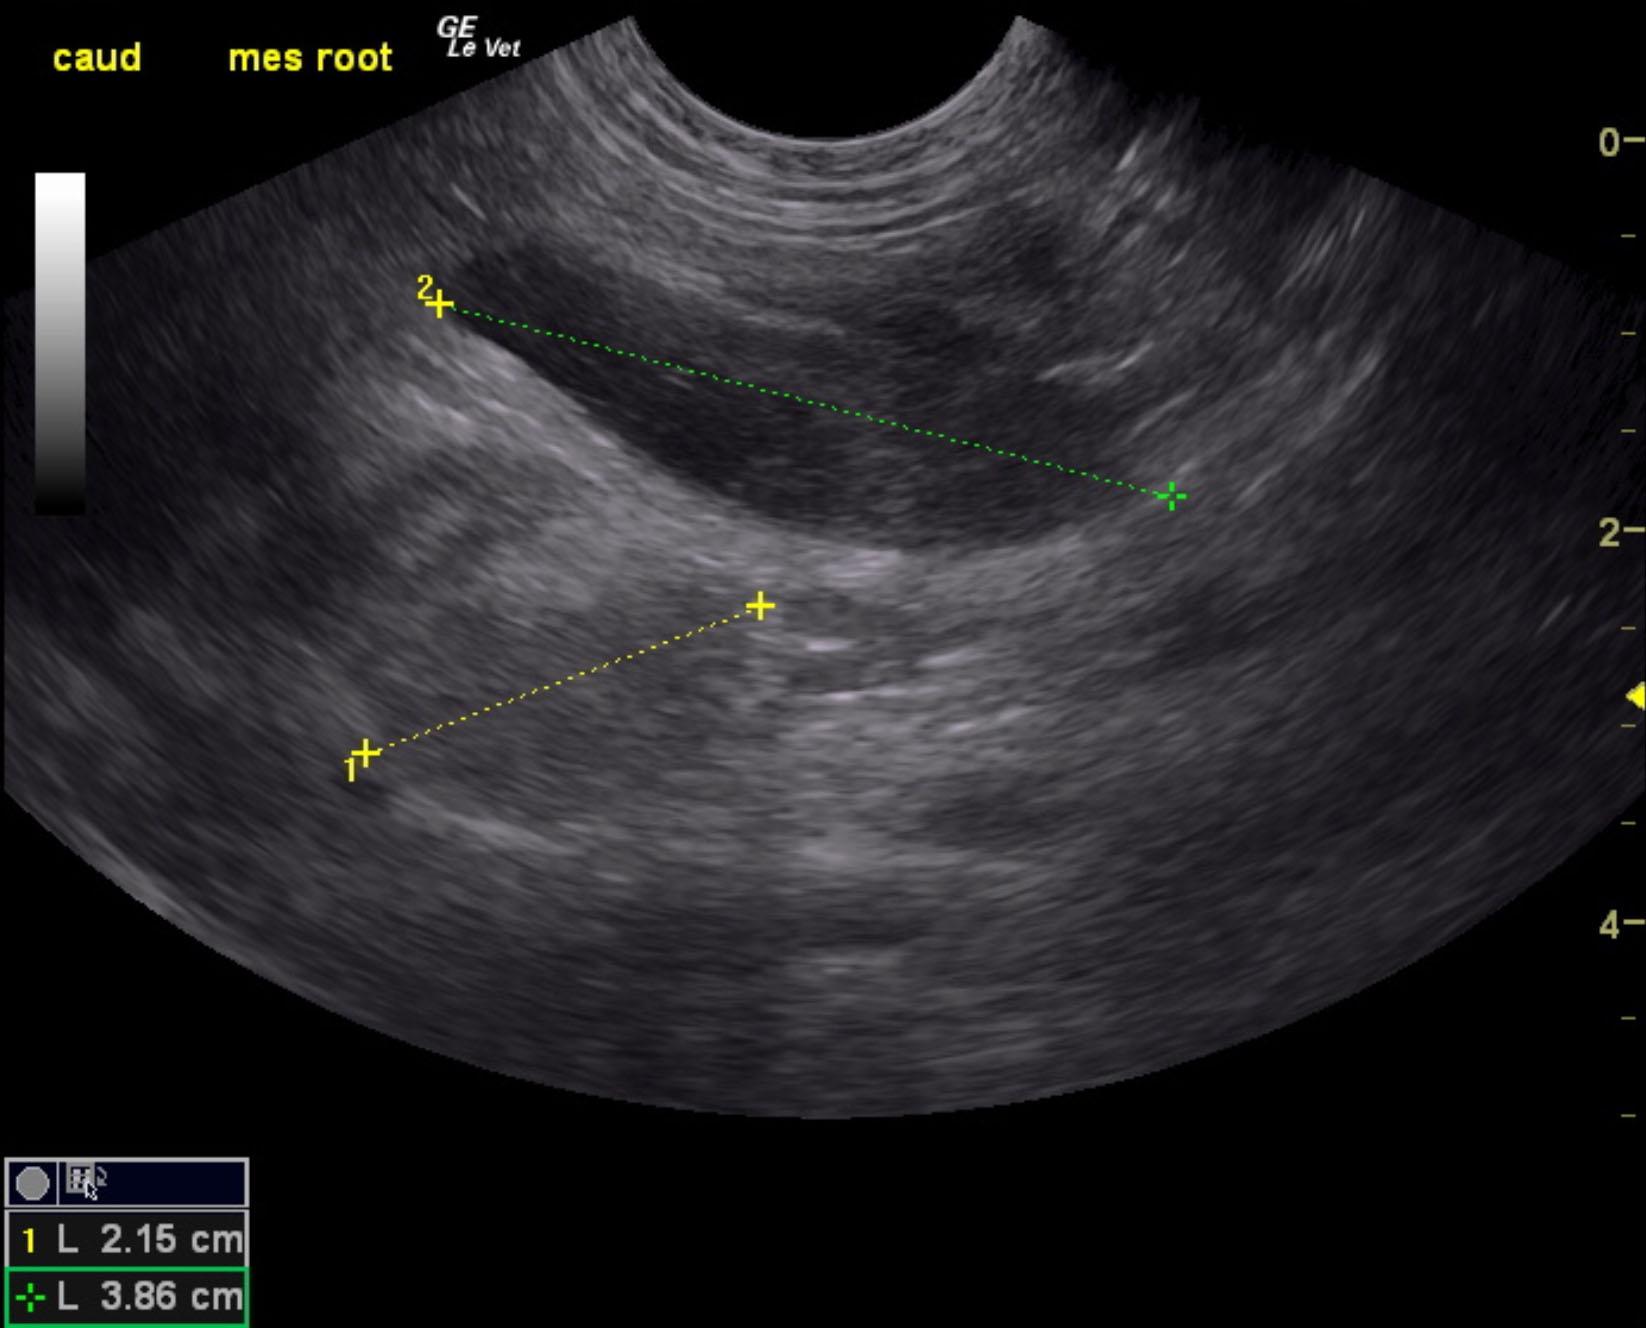

A 6-month-old intact male Labrador was presented for evaluation of diarrhea and vomiting for approximately 1 week and more recently only hemorrhagic diarrhea.